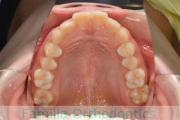

No.22V-398

- 叢生

- 14歳

- 男性

- 抜歯部位

- 上:

- 8448

- 下:

- 主な使用装置:

- FEA 022

- 治療にかかった費用:

- 88万円

八重歯が気になるのを治したいということで来院されました。上下左右から小臼歯を抜歯してマルチブラケット法にて治療を行いました。2年半、30回程度の通院が必要でした。叢生が強く、保定中の後戻りのリスクが高いため、保定がとても重要なケースです。